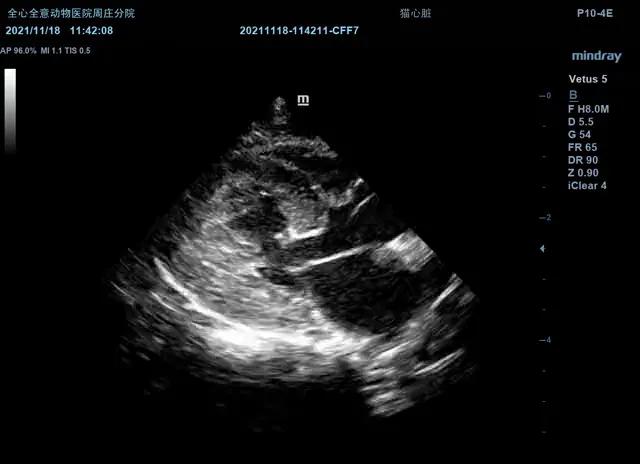

右侧短轴腱索观(2D):

可见乳头肌、肉柱、腱索异常增大。

右侧短轴二尖瓣观(M型):

EPSS:0.11cm

E-F Slope:4.23cm/s

C点至D点二尖瓣运动轨迹异常。